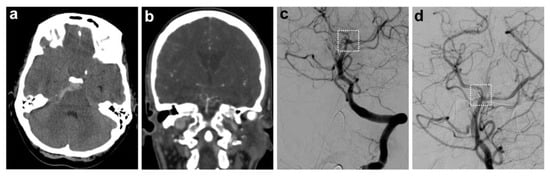

Functional outcomes at discharge were significantly worse in patients with aneurysms. The median mRS at discharge was 1.0 [IQR 0.0–3.5] in the aneurysm group compared to 0.0 [IQR 0.0–0.0] in the non-aneurysm group (p = 0.0077). The GOS was also lower in the aneurysm group (5.0 [IQR 3.0–5.0]) compared to the non-aneurysm group (5.0 [IQR 5.0–5.0], p = 0.0002), reflecting a trend towards worse neurological recovery (Figure 2).

Figure 2.

Functional outcome at discharge in patients with and without aneurysmal pathology. The violin plots show the distribution of modified Rankin scale (mRS) scores (a) and Glasgow Outcome Scale (GOS) scores (b) at hospital discharge, stratified by aneurysm status. While the outcome distribution in patients without aneurysms was tightly clustered around favorable values, the aneurysm group showed a significantly broader distribution with a tendency towards worse outcomes. This pattern reflects greater heterogeneity and more frequent functional impairment in the presence of aneurysmal pathology. Dotted lines indicate medians and shaded areas indicate the density of data points.